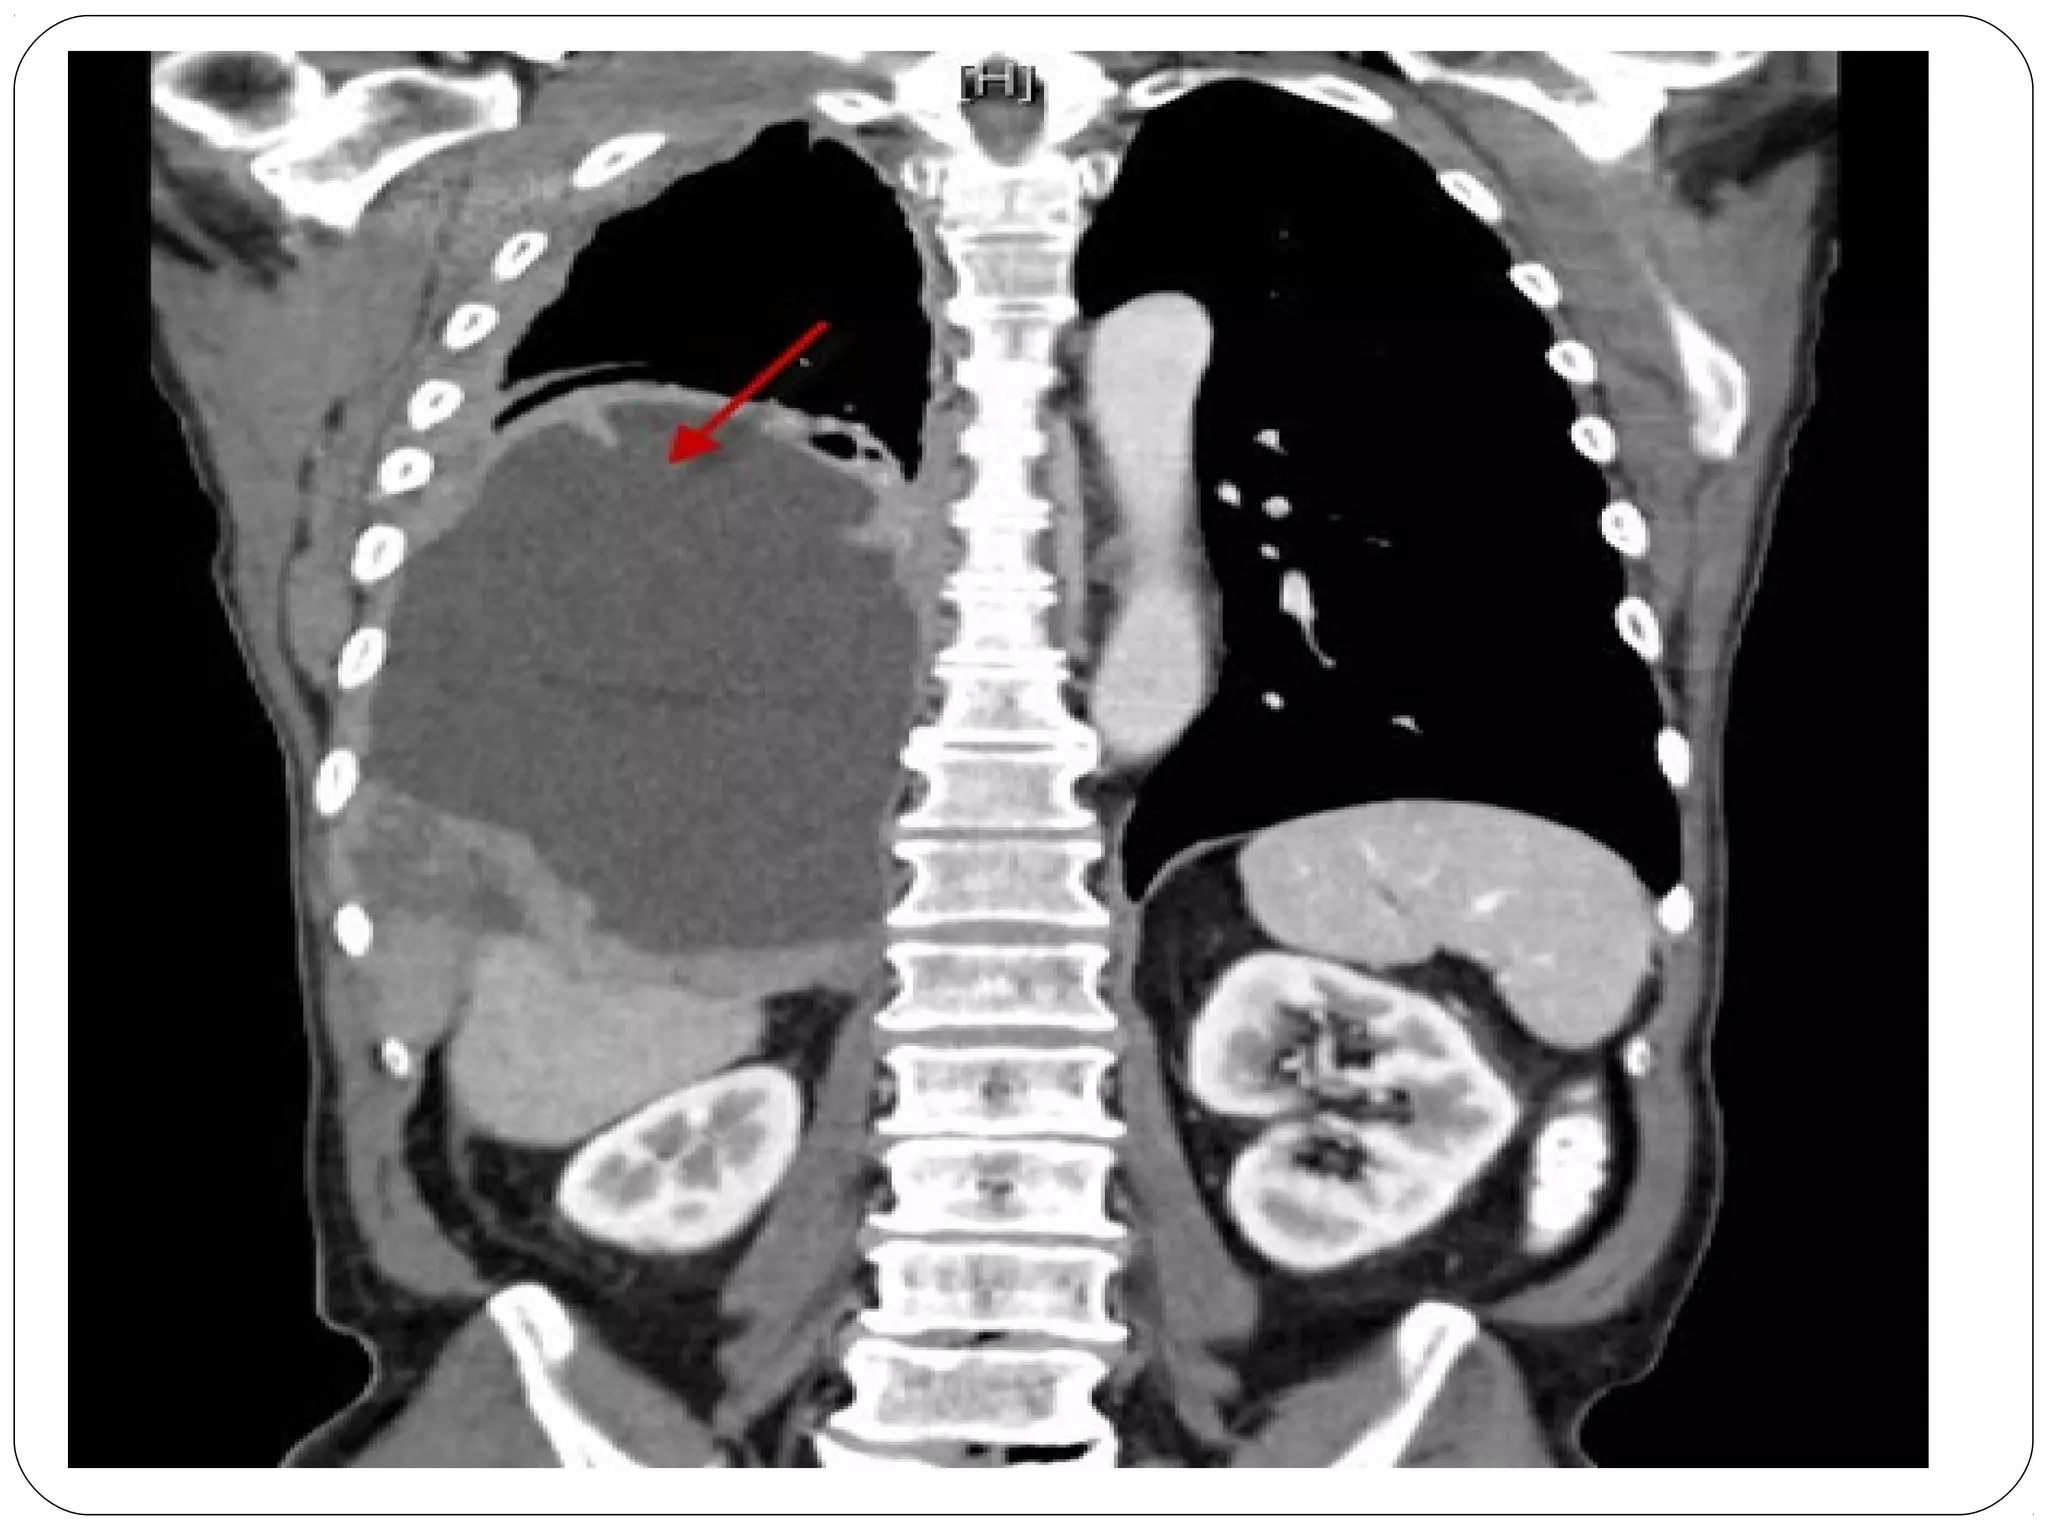

• #52 What color is air on an a X-ray or CT? where is the problem? CT of mesothelioma